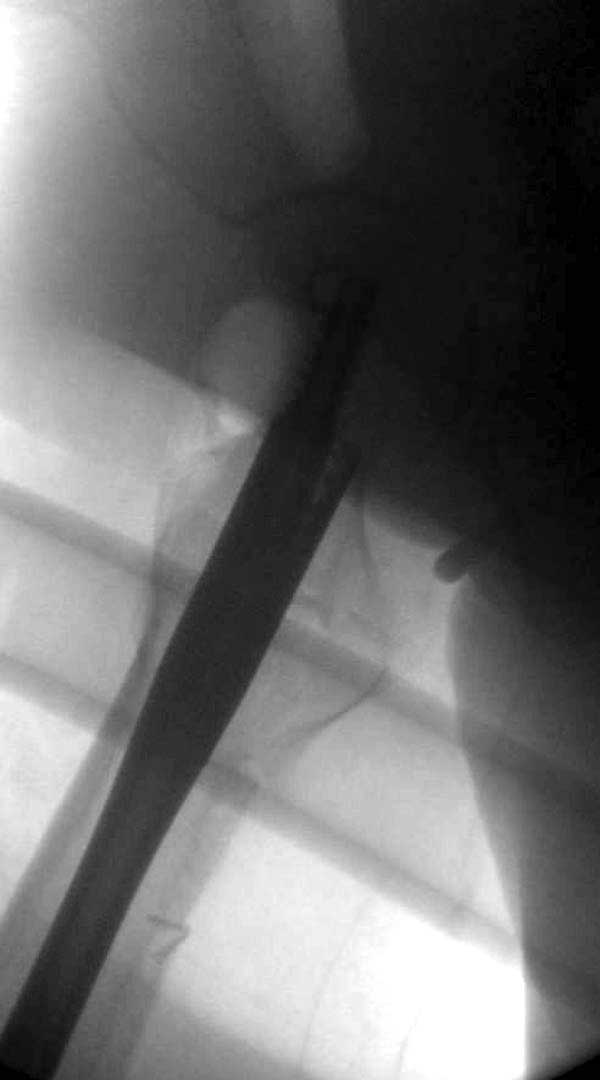

Такие “чужие осложнения” встречаются у всех и представляю банальный случай, который шаг за шагом показано как перерос в более сложный процесс... Больная 70 лет, множественные ко-морбидности, чрезвертельный перелом первоначально фиксирован Гамма 3. Осложнение в течение 6 недель, ревизия тотальной артропластикой и во время установки ножки обнаружена трещина диафиза (17), из малого доступа фиксация алло-графтом.

Обычно после чрезвертельных переломов, за исключением молодых, у пожилых остается нестабильность при движении. Часто падают и после 3х мес. в результате падения обнаружен перипротезный перелом (22-23), который зафиксирован Синтез пластиной.

Повторно поступает после двух с половиной лет, где обнаруживается перелом на второй стороне. Немного сложно, но для фиксации выбрали Antegrade InterTan Smith Nephew Nail и с момента фиксации более 3х мес.